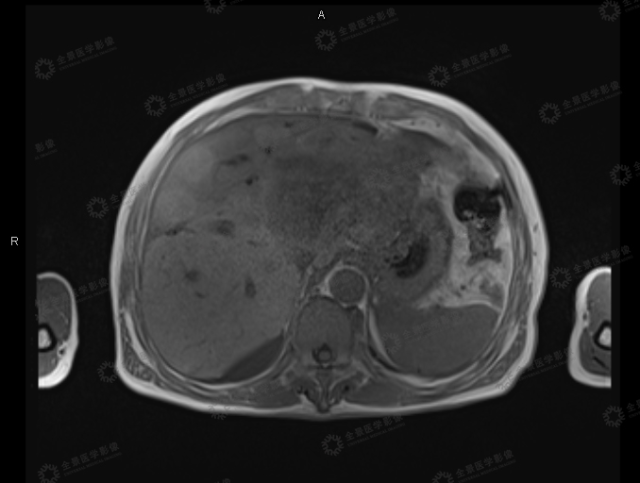

病史:患者男,60岁,肝细胞性肝癌综合治疗后复查,来我中心进行肿瘤复查及肝脏MR定量分析检查。